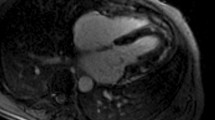

The CMR study was performed on a 3T Philips Achieva system TX equipped with a 32-channel coil. Low resolution survey, reference scans and localisers determined the cardiac short axis, vertical long axis and horizontal long axis with cine imaging (balanced steady state free precession (SSFP) acquisition, see Fig. 1). LV dimensions and function were obtained from cines covering the entire heart in the LV short axis [18, 19] (balanced SSFP, multiphase, contiguous slices, voxel size 1.2 × 1.2 × 10 mm3, 50 cardiac phases).

Typical CMR images from this study including SSFP cine imaging planned in the four chamber view (upper left), high temporal resolution cine imaging for aortic distensibility (lower left), native T1 mapping at mid ventricular level (upper right) and tagged cine imaging for strain analysis (lower right)